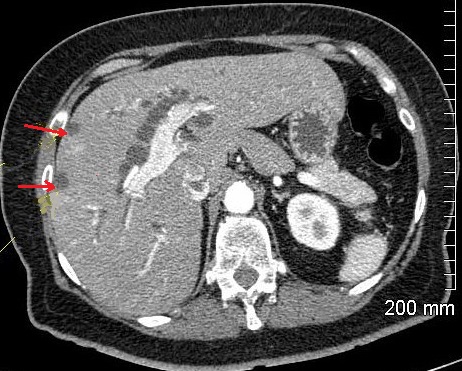

Image TDM

et IRM : Image radiologique

TDM et IRM de cholangite infectueuse c'est :

- La rehaussement nonhomogen de densite du

foie en phase arterielle du CT ,

- Image de dilatation des voies biliaire intra

hepatique ( peut etre central 38% , diffuse

16%,et segmentaire 46% ),

- Une dilatation de la voie biliaire

principale

- Une epaissisement parietal regulier et

systemique des voies biliaires ( superieure a

1.5mm d'epaisseur pour la voie biliaire

principale )

- Une prise de contrast homogene et precoce

des voies biliaires inflammatoires

Aspects arrondies

hypodensite a bord irregulier de deux abces

angiocholite situe du foie droit (

fleche rouge ) . Image radiologique TDM avec

de contrast intraveineuse ( C+ ) en coupe

axiale . |

Image d'une pyleplebite de veine

mesenterique supperieure ( fleche jaune ) .

Sa paroi est epais et hyperdensite

etre en vue tres nette ( fleche jaune ) sur ce coupe . Image radiologique TDM en coupe

coronal ( frontal ) |